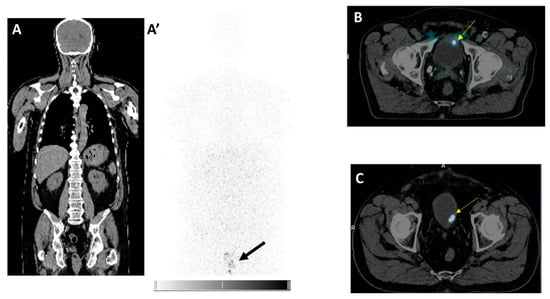

3.5. Clinical Proof of Concept of Intravesical Therapy in Patients: PERTINENCE Study Procedure Using [89Zr]Zr-Girentuximab